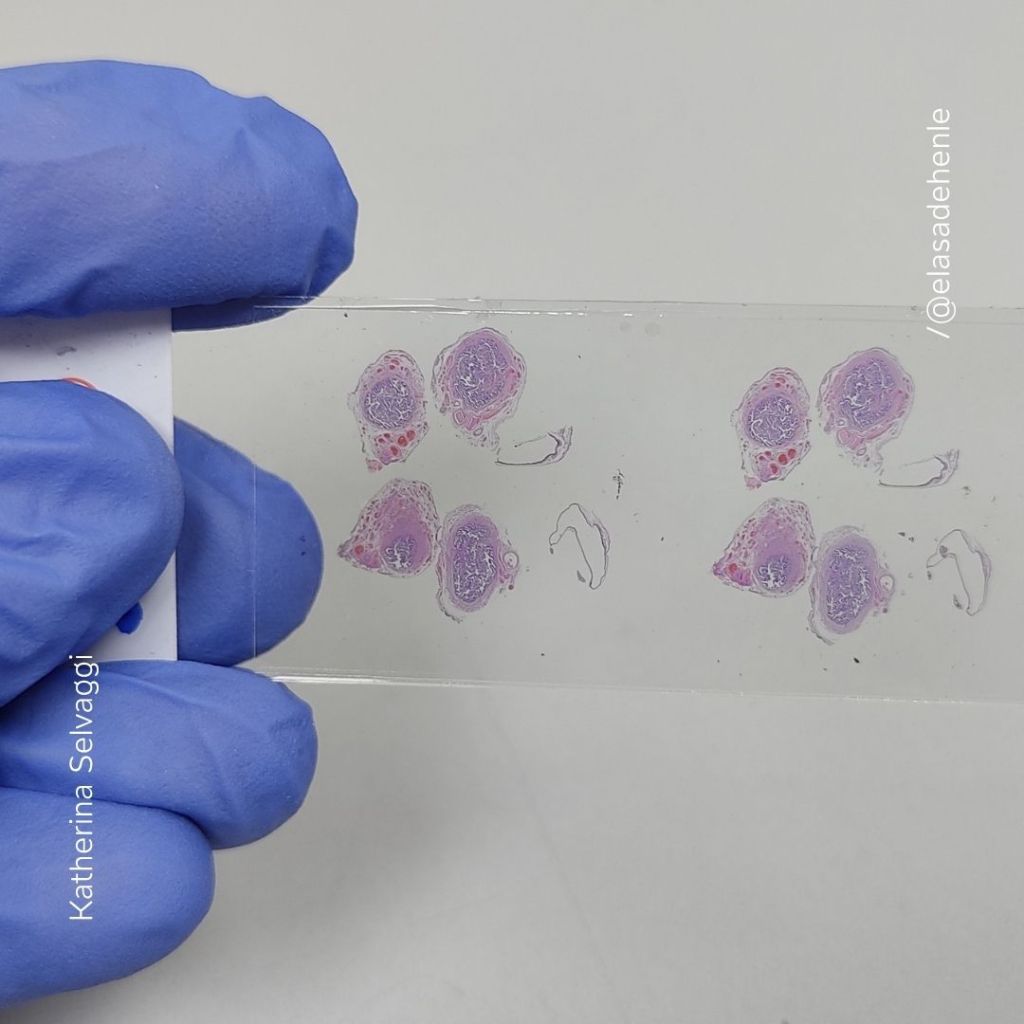

Hematoxilina y eosina

Trompa de Falopio

COMECA